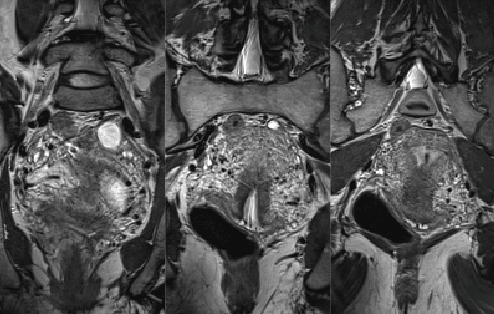

●Higher speed

3Dイメージングに必須なオーバーサンプリング設定が不必要になります。そのため,短いエコートレインによる低組織コントラスト分解能の向上と,大幅な撮像時間の短縮によって,子宮頸がんの広がり診断が期待されています(図4)。

図4 子宮頸部の局所3D画像